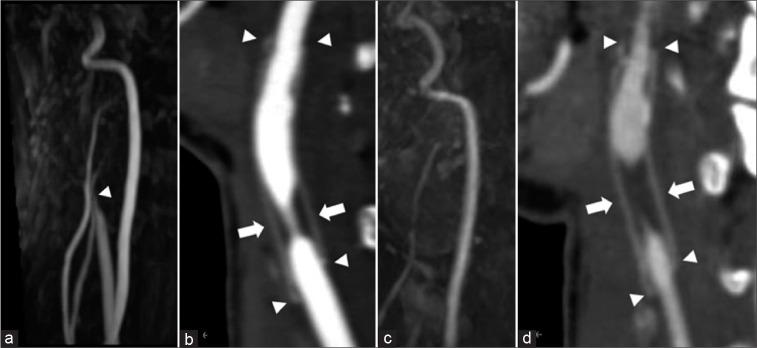

A woman in her 20s experienced injury to the right carotid artery during an operation for removal of a carotid body tumor 6 years before presentation. The right common carotid artery and internal carotid artery were replaced with an artificial vessel graft at that time. Intraluminal stenosis in the graft was not identified 3 years after surgery; however, 4 years after surgery, stenosis was recognized at the non-anastomotic site inside the artificial vessel graft. Subsequently, antiplatelet therapy was initiated. The stenosis was noted to progress gradually in follow-up appointments. Therefore, we decided to intervene because of the patient's young age and the risk of long-term hemodynamic stress. Angiography revealed pseudo-occlusion in the artificial vessel. Percutaneous transluminal angioplasty was performed for stenosis with distal protection; subsequently, CAS was performed. The patient was discharged without neurological deficits 4 days after the operation, and no apparent restenosis was observed as of the 1-year follow-up.

Stenosis after cervical artery replacement can be safely treated with CAS. Inflation pressure and stent should be selected according to the pathology of the stenosis.